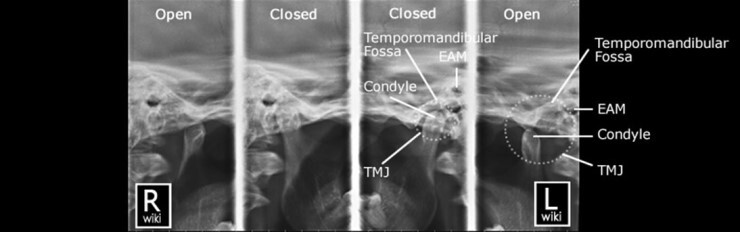

4. TMJ Radiography

| • Trauma Protocol : Lateral Oblique(Mouth open/closed), AP Axial(Towne, Mouth open) -> Supplementary view : Orthopantogram (OPG) • Non Trauma Protocol : Lateral Oblique(Mouth open/closed), AP Axial(Towne, Mouth open) -> Supplementary views : Orthopantogram (OPG) |

1) Adult Lateral Oblique - Closed/Open Mouth

2) Gleb 4/7 position

![]() |

• 하악과두는 앞뒤로 볼 때 턱관절 주머니의 정가운데에서 앞쪽(관절융기 쪽)에 위치 • 위아래로 볼 때 턱관절 주머니의 전체 높이의 절반 정도에 위치 |

3) Adult Temporomandibular Joints - Performed on an OPG Machine